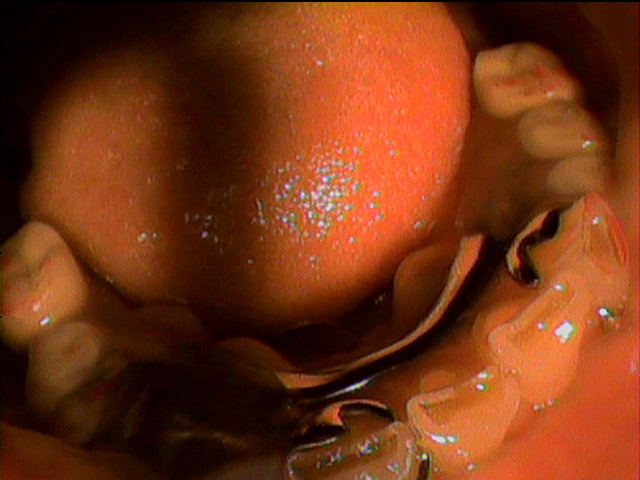

84歳女性のKさんは、下の顎が総入れ歯で、顎の状態が骨が少なく、

状態がよくないために、顎が入れ歯で痛くなりやすく、

コンフォート義歯を入れています。今回上の総入れ歯がやせてきてしまい、

新しく作製しました。上の顎の顎堤の状態は良好ではありませんが、

精密義歯で、いつでも顎の状態の変化に対応できる入れ歯を作製しました。

上の総入れ歯のコンフォート加工の症例です。 |